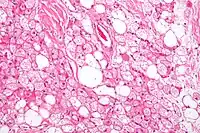

Los tumores se parecen histológicamente a la grasa parda. Se reconocen cuatro tipos histológicos, pero uno es el más frecuente (típico). Se observa un entorno rico en vascularización .

- Tipo lobulillar: grados variables de diferenciación de células uniformes, redondas a ovaladas con células eosinófilicas granulares con bordes prominentes, que se alternan groseramente con adipocitos multivacuolados. Por lo general, hay pequeños núcleos ubicados en el centro sin pleomorfismo. Las células tienen grandes gotas de lípidos citoplasmáticos grandes diseminados por todas partes.[1][2]

- Variante mixoide: matriz basófila suelta, con septos fibrosos gruesos e histiocitos espumosos.